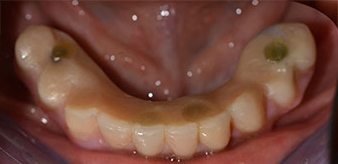

Una vez transcurrido el tiempo necesario para la integración ósea, puede llevarse a cabo la impresión definitiva del implante para realizar la prótesis definitiva de manera acorde (figs. 19 y 20). En este paso, el responsable del tratamiento y el paciente pueden decidir conjuntamente si es preferible un revestimiento cerámico o plástico y una estructura de zircón o de metal. En este caso, dado que el pronóstico de la dentición del maxilar superior era poco claro y la pieza dental 24 estaba elongada, el equipo del Dr. Pascu se decidió por un revestimiento de plástico, ya que, por lo general, es mucho más fácil de ajustar y puede adaptarse a la nueva situación del maxilar superior.

integración ósea

Fig. 19

Implantes

Fig. 20